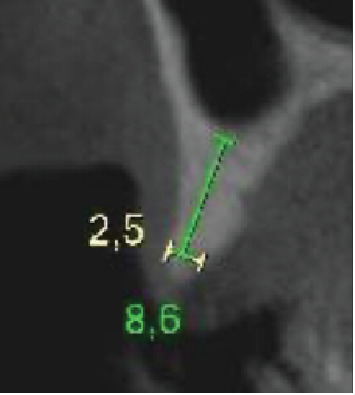

背景:缺牙是一个世界性的问题,影响患者的社会和功能。种植体康复是金标准治疗;然而,可能需要先进行骨重建。杠铃技术是一种引导骨再生技术,推荐用于各种形态的缺陷,允许垂直和水平单向或双向再生,即在颊侧和腭侧/舌侧。本文的目的是报告一例在种植体康复之前的后上颌骨重建,其中杠铃技术与窦提升一起进行。方法:本研究报告了一名77岁男性患者,其右侧第一和第二双尖缺失,并有种植体丢失的历史。最初的CT扫描显示水平和垂直牙槽萎缩,使种植体无法放置。采用鼻窦提升术进行垂直恢复,Barbell技术进行水平再生,使用胶原膜覆盖的异种骨。6个月后,新的CT扫描显示骨容量足够,并根据数字计划引导放置两个植入物。结果:植骨前后的CT扫描显示水平骨增重70%,垂直骨增重33%。重建手术6个月后,植入牙种植体,45天后安装单个冠。在24个月的随访中,未观察到与种植体或假体相关的并发症。结论:在这个临床病例中,这是文献中第一次,这些技术的结合使缺损再生,随后将植入物放置在理想位置并进行假肢康复。

Background: Dental absences are a worldwide issue, affecting patients both socially and functionally. Implant rehabilitation is the gold standard treatment; however, prior bone reconstructions may be necessary. The Barbell Technique is a guided bone regeneration technique recommended for defects of various morphologies, allowing for vertical and horizontal unidirectional or bidirectional regeneration, that is, both on the buccal and palatal/lingual sides. The objective of this paper is to report a case of bone reconstruction in the posterior maxilla prior to implant rehabilitation, where the Barbell Technique was performed together with a sinus lift. Methods: This study consists of a case report of a 77-year-old male patient with the absence of first and second right bicuspids and a history of implant losses in the area. The initial CT scan showed horizontal and vertical alveolar atrophy, making implant placement impossible. Regeneration was performed using a sinus lift for vertical recovery and the Barbell Technique for horizontal regeneration, using xenogeneic bone covered by a collagen membrane. After 6 months, a new CT scan suggested sufficient bone volume, and two implants were guidedly placed based on digital planning. Results: Comparison of CT scans before and after the grafts showed a horizontal bone gain of 70% and a vertical gain of 33%. Six months after the reconstructive surgery, dental implants were placed, followed by the installation of individual crowns after 45 days. At the 24-month follow-up, no complications related to the implants or prostheses were observed. Conclusion: In this clinical case, for the first time in the literature, the association of the techniques allowed the regeneration of the defect, with the subsequent placement of implants in the ideal position and prosthetic rehabilitation.